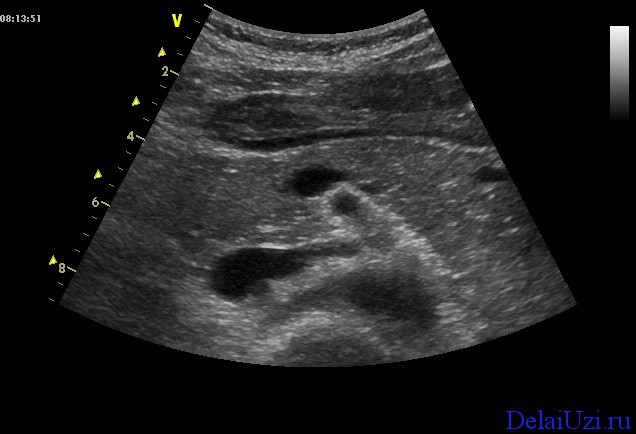

Дуплексное сканирование позволит оценить крупные сосуды находящиеся рядом с исследуемым органом. Особенность этого типа исследования показывает качество кровотока в нижней полой вене, в верхних брыжеечных вене и артерии, в чревном стволе и селезеночной вене. Расшифровка показаний при дуплексном сканировании говорит о том, страдает ли орган от недостаточного тока крови и есть ли препятствия на пути потока в виде опухолей. Если такие изменения имеются, нужно замерить их размеры и структуру ткани.

Особую важность представляет состояние протока железы (Вирсунгов проток). Если есть какие-либо изменения, то возникают подозрения на опухоль головки железы или панкреатит.

Первый этап заболевания характеризуется увеличением размеров железы. Контуры становятся нечеткими, а панкреатический проток значительно расширяется. Часто патологические изменения затрагивают и соседние органы, что также приводит к повышению их эхогенности. Увеличенная поджелудочная железа может сжимать крупные сосуды, нарушая кровоснабжение близлежащих органов. Эти изменения хорошо видны при дуплексном сканировании, даже если пациент не подготовился должным образом.